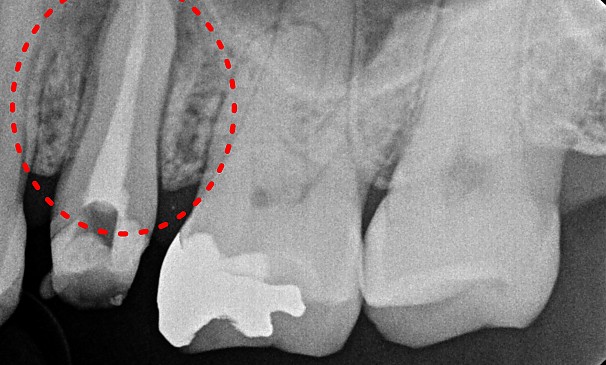

특수재신경치료

최OO님 전후사진 | 치료 기간 : 1주

치료 전

치료 후